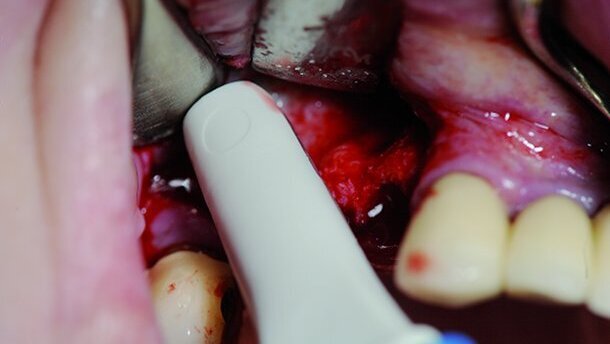

Le matériau de greffe doit être inséré en commençant par les zones les plus difficiles d’accès et mis en contact avec les parois osseuses, afin de garantir une meilleure cicatrisation de l’os. Si la membrane sinusienne (membrane de Schneider) est très mince, elle doit être protégée et stabilisée avec une membrane de collagène.

Les dépressions sont d’abord comblées dans les parties antérieures et postérieures, puis la région de la paroi médiale du sinus est à son tour comblée. Le greffon ne doit pas trop surélever la membrane et ne doit pas être trop compacté, pour ne pas entraver la vascularisation, surtout en présence de biomatériaux. Les implants sont ensuite insérés l’un après l’autre dans les cavités implantaires préparées. Ceci permet le compactage du tissu spongieux relâché de l’os maxillaire, après que le trou de guidage pratiqué dans l’os de qualité médiocre, ait été préparé au moyen de compacteurs d’os. C’est également une façon utile et efficace d’améliorer la stabilité primaire.

Après l’insertion des implants du côté latéral, le greffon est placé sur les implants, tout l’espace intermédiaire et les cavités sont comblés et la fenêtre osseuse est recouverte d’une petite membrane de collagène. La taille de cette membrane doit correspondre à la fenêtre osseuse réelle. La fixation peut être réalisée sans utiliser de tenons ou de sutures résorbables sous le lambeau mucopériosté.